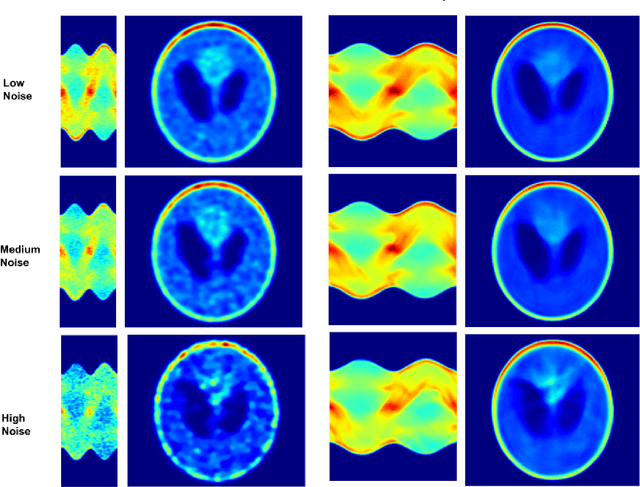

Abstract:A novel method for SPECT angle interpolation based on deep learning methodologies is presented. Projection data from software phantoms were used to train the proposed model. For evaluation of the efficacy of the method, phantoms based on Shepp Logan, with various noise levels added were used, and the resulting interpolated sinograms are reconstructed using Ordered Subset Expectation Maximization (OSEM) and compared to the reconstructions of the original sinograms. The proposed method can quadruple the projections, and denoise the original sinogram, in the same process. As the results show, the proposed model significantly improves the reconstruction accuracy. Finally, to demonstrate the efficacy and capability of the proposed method results from real-world DAT-SPECT sinograms are presented.